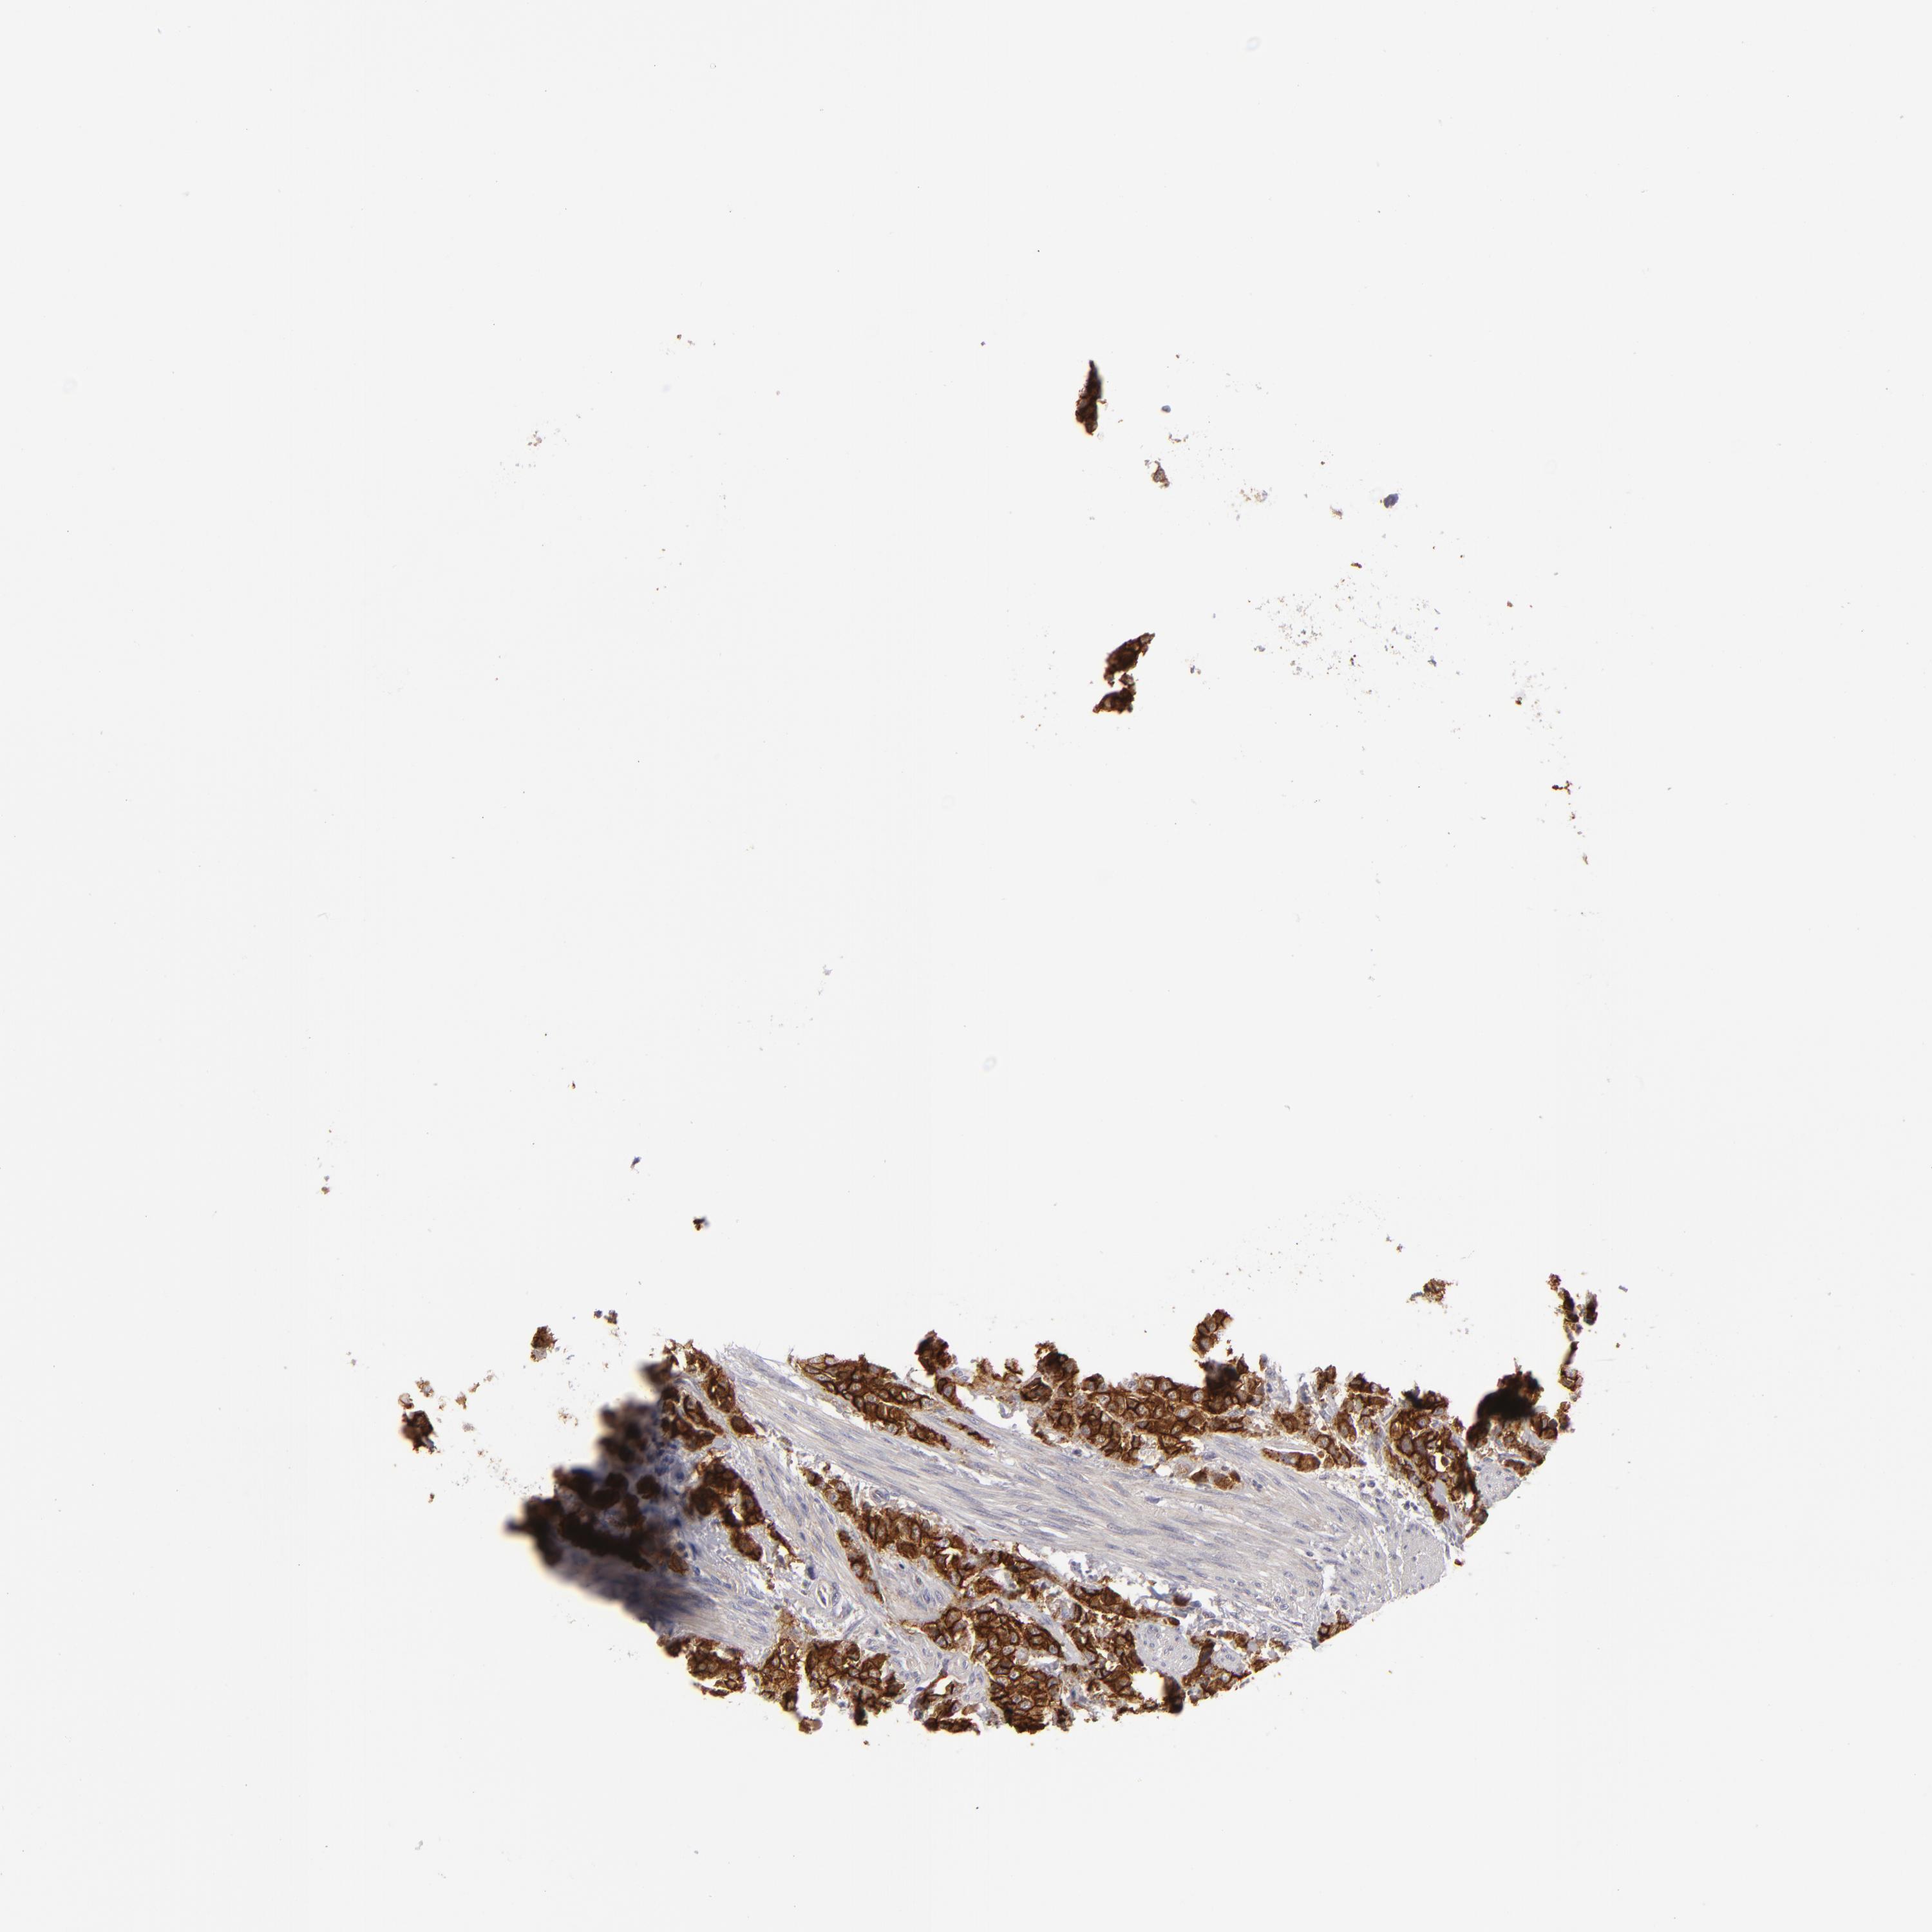

UROTHELIAL CANCER - Protein expressioni

A mouse-over function shows sample information and annotation data. Click on an image to view it in a full screen mode. Samples can be filtered based on level of antibody staining by selecting one or several of the following categories: high, medium, low and not detected. The assay and annotation is described here.

Note that samples used for immunohistochemistry by the Human Protein Atlas do not correspond to samples in the TCGA dataset.

Antibody stainingi

Antibody staining in the annotated cell types in the current human tissue is reported as not detected, low, medium, or high, based on conventional immunohistochemistry profiling in selected tissues. This score is based on the combination of the staining intensity and fraction of stained cells.

Each image is clickable and will lead to virtual microscopy that enables deeper exploration of all samples and also displays staining intensity scores, fraction scores and subcellular localization as well as patient and tissue information for each sample.

Antibody HPA010926

Antibody CAB002148

Urothelial carcinoma, Low grade

Urothelial carcinoma, High grade

Adenocarcinoma, NOS